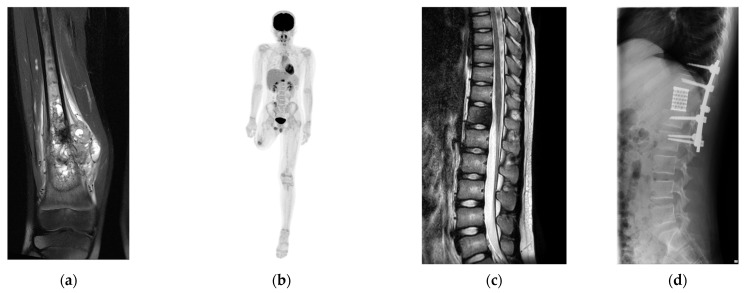

冷冻治疗可刺激免疫反应,诱发体外效应。一种治疗脊柱骨肿瘤的新技术被开发出来,包括使用冷冻肿瘤的自体骨移植物在全椎体切除后进行前脊柱重建,目的是激活冷冻免疫。本研究的重点是分析手术后t细胞受体(TCR)库的变化,以评估t细胞多样性。术前和术后采集血样,进行RNA提取和免疫测序。与术前样本相比,TCR α链和β链的互补决定区3的多样性和丰度下降,表明可能出现了更多选择性克隆并影响了免疫反应。通过TCR库分析,本研究表明冷冻含瘤自体骨移植对免疫系统有影响。这项研究有望为开发可能增强免疫激活的治疗方法提供基础。